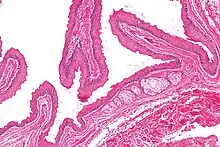

Micrograph of a steatocystoma showing the characteristic corrugated eosinophilic lining. H&E stain